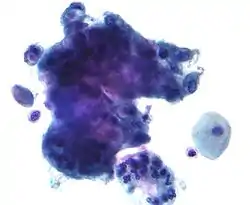

Mucins (/ˈmjuːsɪn/) are a family of high molecular weight, heavily glycosylated proteins (glycoconjugates) produced by epithelial tissues in most animals.[1] Mucins' key characteristic is their ability to form gels; therefore they are a key component in most gel-like secretions, serving functions from lubrication to cell signalling to forming chemical barriers.[1] They often take an inhibitory role.[1] Some mucins are associated with controlling mineralization, including nacre formation in mollusks,[2] calcification in echinoderms[3] and bone formation in vertebrates.[4] They bind to pathogens as part of the immune system. Overexpression of the mucin proteins, especially MUC1, is associated with many types of cancer.[5][6]

Increased mucin production occurs in many adenocarcinomas, including cancers of the pancreas, lung, breast, ovary, colon and other tissues. Mucins are also overexpressed in lung diseases such as asthma, bronchitis, chronic obstructive pulmonary disease (COPD) or cystic fibrosis.[24] Two membrane mucins, MUC1 and MUC4 have been extensively studied in relation to their pathological implication in the disease process.[25][26][27] Mucins are under investigation as possible diagnostic markers for malignancies and other disease processes in which they are most commonly over- or mis-expressed.